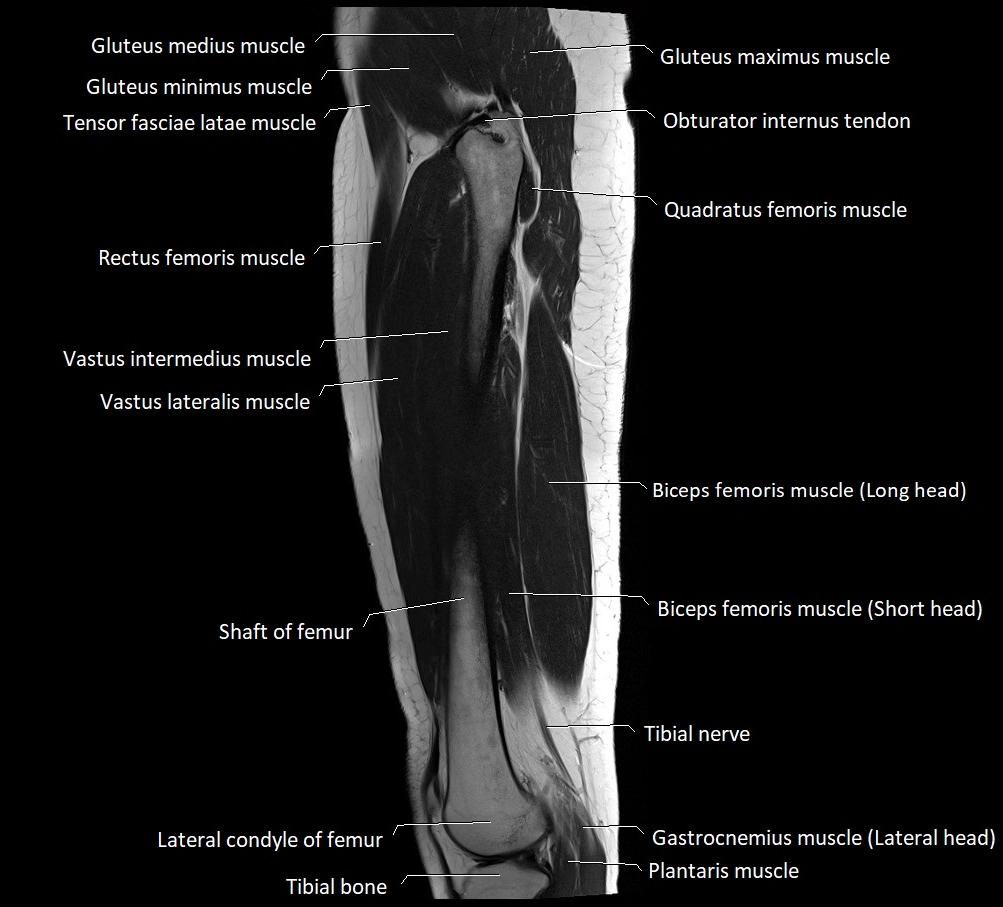

- Biceps femoris muscle (Long head)

- Biceps femoris muscle (Short head)

- Femoral shaft

- Gastrocnemius muscle

- Gluteus maximus muscle

- Gluteus medius muscle

- Gluteus minimus muscle

- Rectus femoris muscle

- Tensor fasciae latae muscle

- Tibial nerve

- Vastus intermedius muscle

- Vastus lateralis muscle